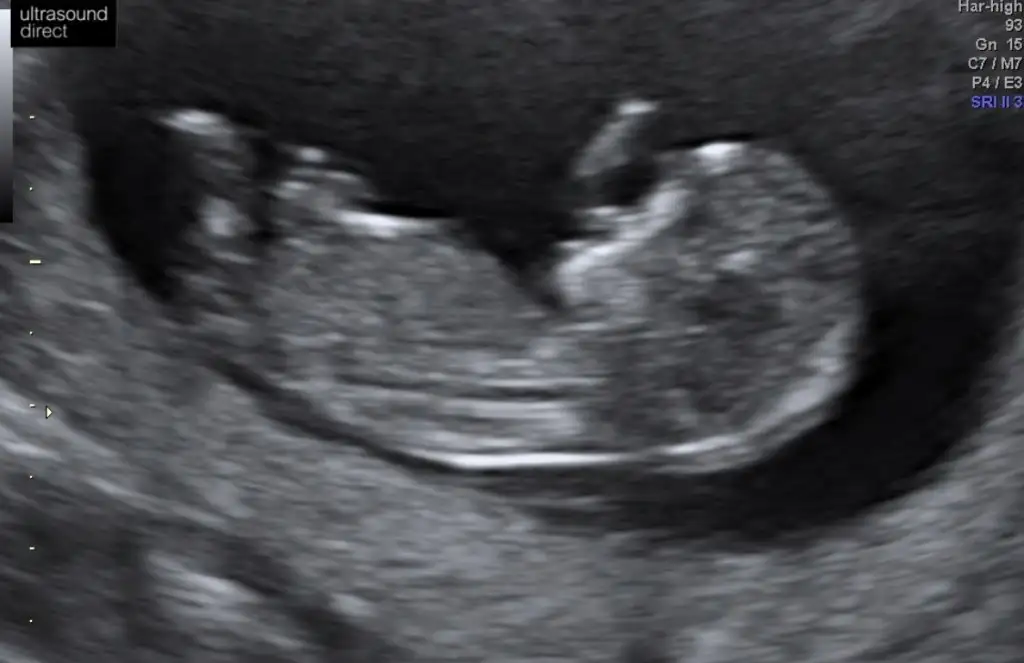

Daha önce ne dedim bilmiyorum burada nub paralel görünüyor kız gibi 12+ usg olursa paylaşınEki Görüntüle 2574907 Eki Görüntüle 2574908 Eki Görüntüle 2574909 Canım 11+1ız sabah dayanamadık doktora gıttık.cınsıyetı bellı degl ama eşim cok merak edıyor sor bakalım dıyor nub a göre neymıs cınsıyetı dıyebıze tekrar bakarsan cok sevınırım

Daha önce erkek demıstınız ama o zaman 10 haftalıktı.12.haftayı paylaşacağım cok teşekkürlerDaha önce ne dedim bilmiyorum burada nub paralel görünüyor kız gibi 12+ usg olursa paylaşın

11 yada 12 hafta tekrar paylaşırsınız şimdilik erkek ama 12 hafta tahminimi onaylarız

Erkek olduğunu tahmin ediyorum